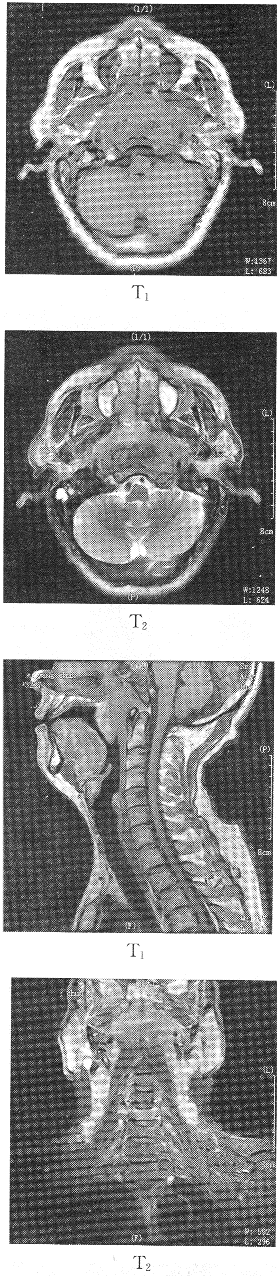

2.患者男性,64歲,反復(fù)鼻出血3個月,伴頭痛耳鳴1個月余,患者行MR圖像如下,最有可能的診斷是

正確答案:C 解題思路:鼻咽部6cm腫塊,TWI低信號,TWI等信號,頸部淋巴結(jié)明顯廣泛腫大。淋巴瘤鼻咽部一般無腫塊,顱咽管瘤多發(fā)生在鞍區(qū),鼻咽纖維血管瘤頸部淋巴結(jié)不大。